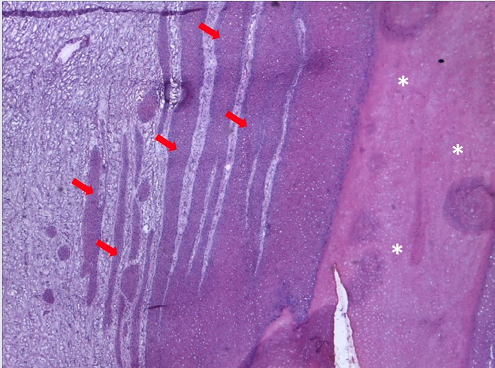

Em casos de acometimento tumoral mais profundo, é possível identificar, abaixo do subcutâneo e da gálea aponeurótica, tecido conjuntivo denso, com fibras colágenas e fibroblastos, representando o periósteo (Figura 1b).4